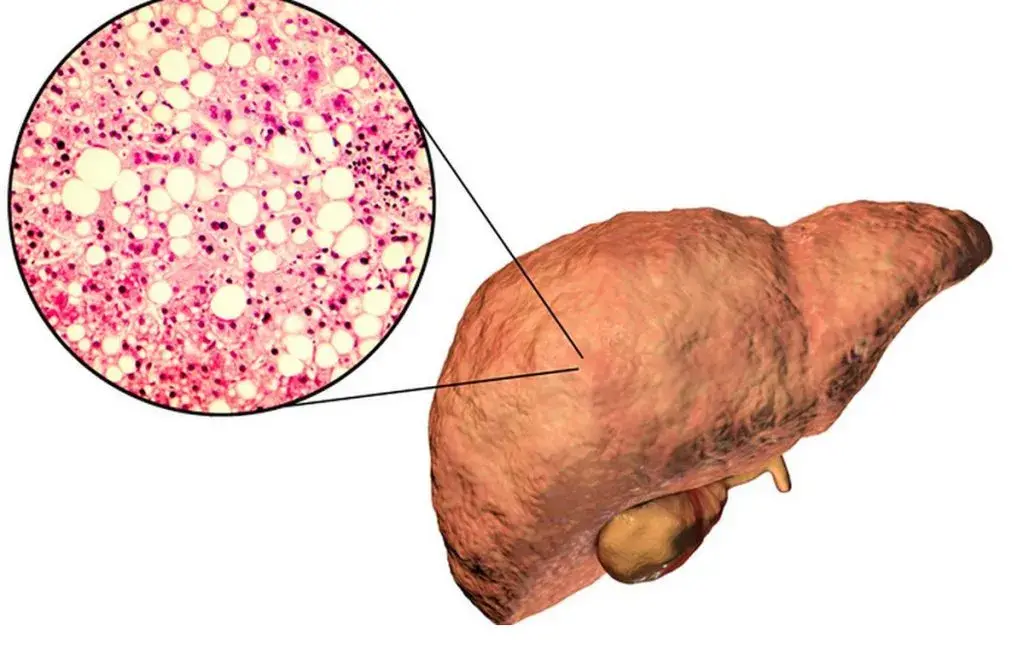

عامل دیگر کبد چرب غیرالکلی (NAFLD) است که در اثر تجمع چربی در کبد رخ میدهد و گاهی میتواند التهاب (استئاتوهپاتیت غیرالکلی) ایجاد کند. این حالت بیشتر در افراد چاق یا دیابتی دیده میشود و میتواند به فیبروز و سیروز کبدی پیشرفت کند. اگرچه کبد چرب غیرالکلی در دسته علل هپاتیت مزمن قرار میگیرد، ولی اغلب آهستهتر پیش میرود و با اصلاح شیوه زندگی (رژیم غذایی، ورزش و کاهش وزن) قابل بهبود است.

هپاتیت B از این جهت خطرناک است که میتواند مزمن شود و به سیروز (التهاب مزمن و سخت شدن بافت کبد) یا سرطان کبد منجر گردد. آمارها نشان میدهد هپاتیت B شایعترین علت سیروز و سرطان کبد در جهان است. همانطور که اشاره شد، این ویروس هر سال باعث مرگ بیش از یک میلیون نفر در دنیا میشود. خوشبختانه واکسن مؤثر برای پیشگیری از هپاتیت B وجود دارد که بعداً به آن میپردازیم.

مشکل اصلی زمانی رخ میدهد که ویروس در بدن باقی بماند و عفونت مزمن ایجاد کند. حدود ۵ تا ۱۰ درصد افراد بزرگسال مبتلا به هپاتیت B، ویروس را از بدن خود پاک نمیکنند و به حالت مزمن میرسند. در عفونت مزمن ممکن است سالها هیچ علامت خاصی دیده نشود، اما ویروس بهآهستگی به کبد آسیب میرساند. در درازمدت، هپاتیت B مزمن میتواند باعث سیروز (تنبلی کبد) یا سرطان کبد شود. این عوارض میتوانند مرگبار باشند. هپاتیت B بهقدری شایع و پرخطر است که در حال حاضر بیش از ۲۵۰ میلیون نفر ناقل مزمن آن در جهان زندگی میکنند.